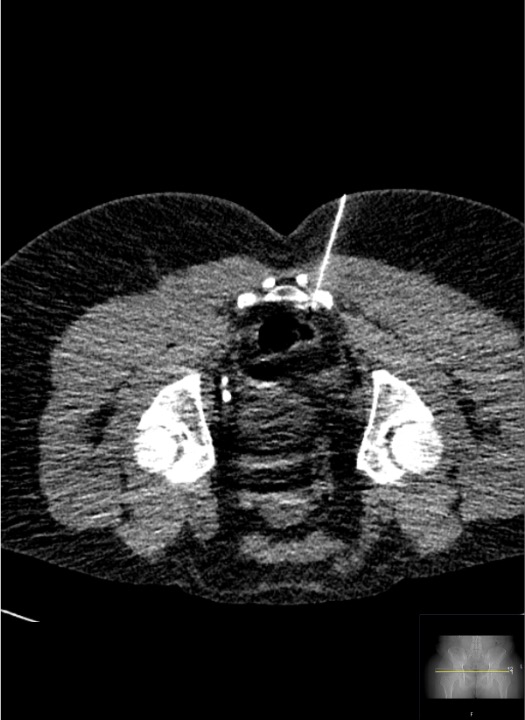

SHP Target — CT Anatomy

- Primary target: retroperitoneal fat space directly anterior to the L5-S1 intervertebral disc, medial to the common iliac artery bifurcation

- Bilateral needle configuration: two Chiba needles form a "V" with tips converging at the L5-S1 anterior disc/junction

- Depth guide: on axial CT, tips should be in the retroperitoneal fat immediately anterior to the psoas and vertebral body, posterior to the iliac vessels